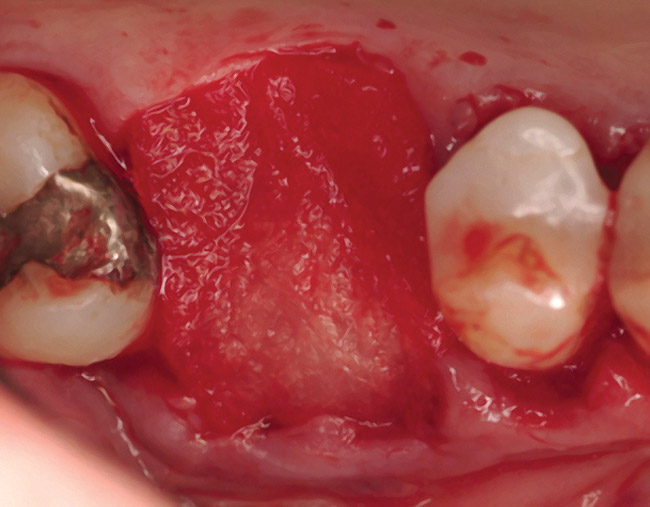

The patient was a 71-year-old man with significant caries and subsequent bone loss associated with tooth No. 30. The septal bone was lost, with the exception of the coronal aspect, resulting in a "bridge of bone" connecting the buccal and lingual cortices of the site (Figure 1). After reflection of the full-thickness buccal and lingual flaps, extraction, and manual and ultrasonic debridement of the socket to remove all visible soft-tissue remnants, the defect was obturated with the rhBMP-2/ACS material (Figure 2).